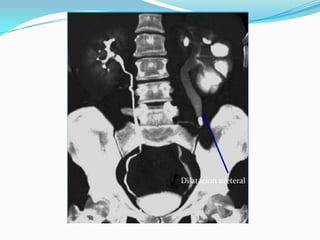

Dilatacion ureteral

 En lasinfecciones urinarias recurrentes de los niños se deberá descartar siempre una malformación.  Se denomina nefropatía por reflujo a la lesión córtico- medular renal resultante del mecanismo de reflujo, la que corresponde a una hidroureteronefrosis frecuentemente con pielonefritis crónica.